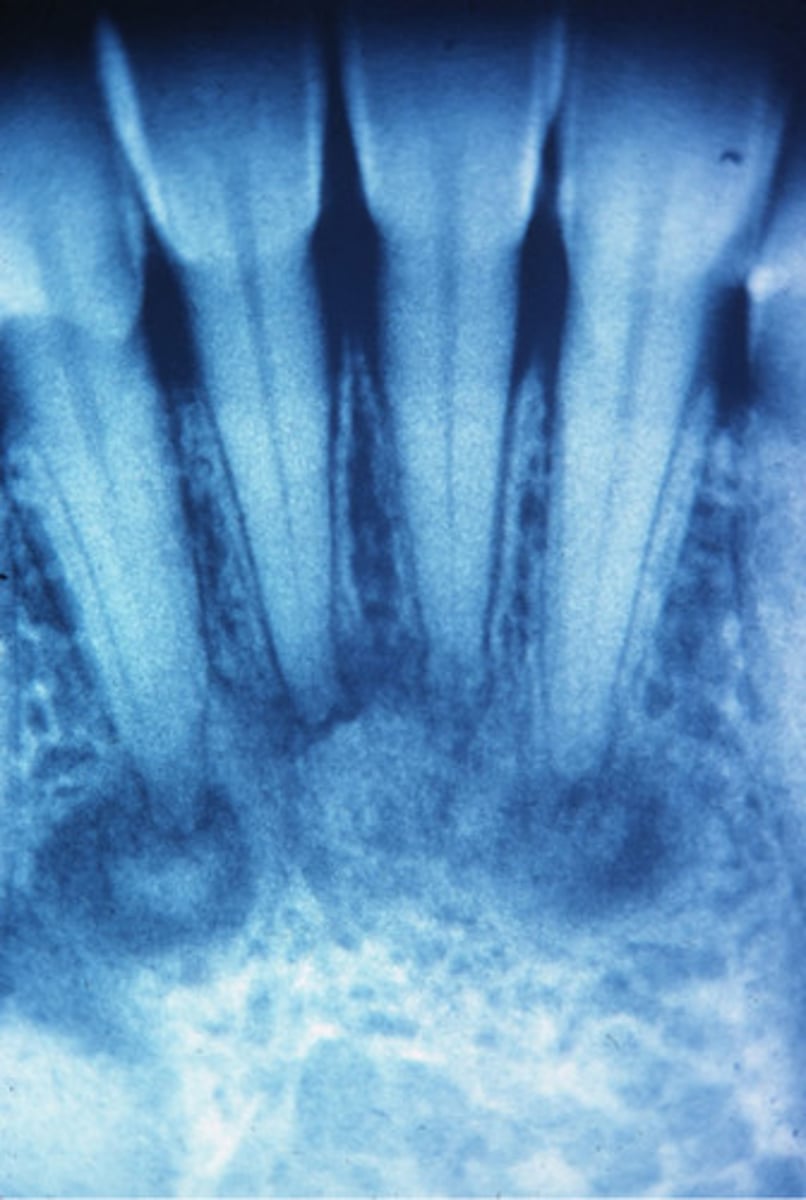

Periapical Cemental Dysplasia

localized change of normal cancellous bone with fibrous tissue and cementum-like material

Clinical Features of Periapical Cemental Dysplasia?

middle aged woman

african american, asian

Vital Teeth

Location of Periapical Cemental Dysplasia

Apex, mandibular anterior teeth

Periphery of Periapical Cemental Dysplasia

well defined,RL border

Internal structure of Periapical Cemental Dysplasia

early stage (apical RL), mixed stage, mature